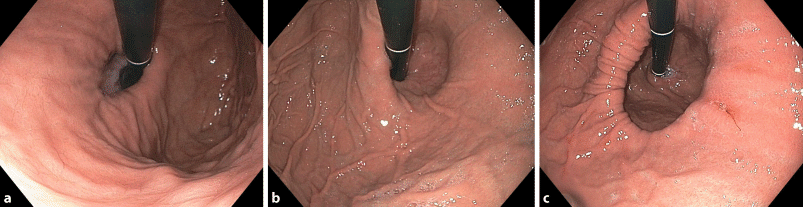

With effect from August 2012, all endoscopists in the department were encouraged not only to describe a HH (Fig. 1), but also to assess the gastroesophageal junction in a retroflexed position and grade it from I to IV according to the grading system described by Hill et al. [9]. Patients whose endoscopic findings were classified as Hill grade I and II were considered to have a normal and grade III and IV to have an abnormal GEFV. Only if endoscopists described a sliding hernia (separation of the squamocolumnar junction = Z‑line from diaphragmatic impression >2 cm) and an abnormal valve were the patients concerned included.

Fig. 1

Examples of different sized hiatal hernias in esophagogastroduodenoscopy (a small; b medium; c large)